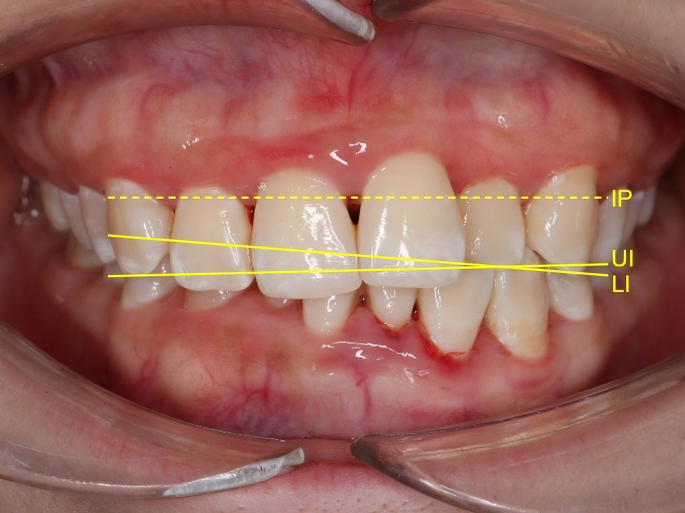

The inclusion criteria were: (1) patients undergoing fixed orthodontic treatment, (2) presence of a cant of the lower incisal plane relative to the upper incisal plane (CLIUI) of at least 1.63°, as measured on standardized frontal intraoral photographs (Fig. 1), and (3) permanent dentition with fully erupted anterior teeth. The exclusion criteria included: (1) clinical signs or symptoms of temporomandibular disorders, including joint click, pain, or restricted mouth opening, (2) history of craniofacial trauma or surgery, and (3) presence of significant skeletal asymmetry or systemic conditions affecting craniofacial growth.

Our analysis focused on six angular and linear variables, three measured at the incisal level and three at the gingival margin (Fig. 3). The incisal level measurements included the cant of the upper incisal plane to the inter-pupillary line (CUIIP), the cant of the lower incisal plane to the upper incisal plane (CLIUI), and the cant of the lower incisal plane to the inter-pupillary line (CLIIP). Similarly, the gingival margin level measurements were the cant of the upper incisal gingival margin to the inter-pupillary line (CUIGIP), the cant of the lower incisal gingival margin to the upper incisal gingival margin (CLIGUIG), and the cant of the lower incisal gingival margin to the inter-pupillary line (CLIGIP). To ensure that positive and negative changes would not negate each other, cants in the same direction as CLIUI at T1 were assigned positive values, while those in the opposite direction received negative values. Additionally, the changes in vertical dimension between T2 and T0 were recorded using the sella-nasion-to-mandibular plane (SNMP) angle measured on lateral cephalograms.